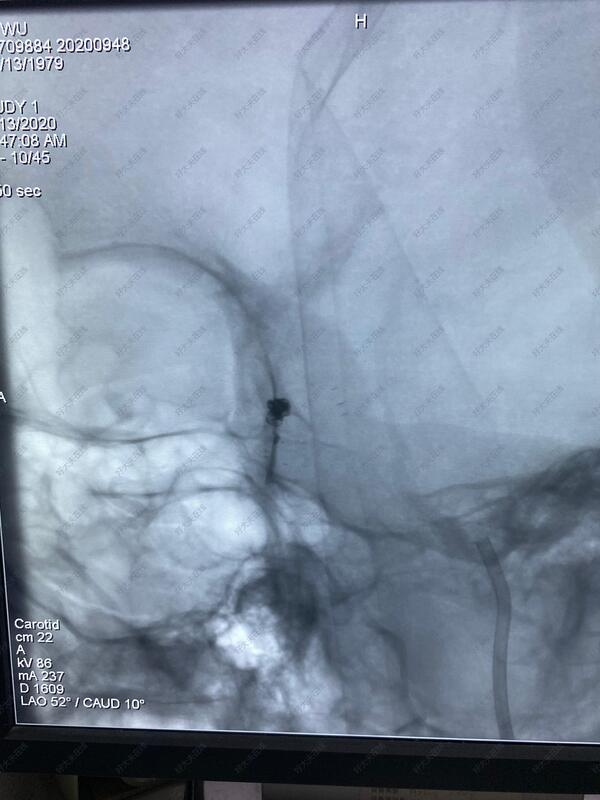

治疗中

采用支架辅助血管内介入栓塞治疗,微创,效果好,恢复快!